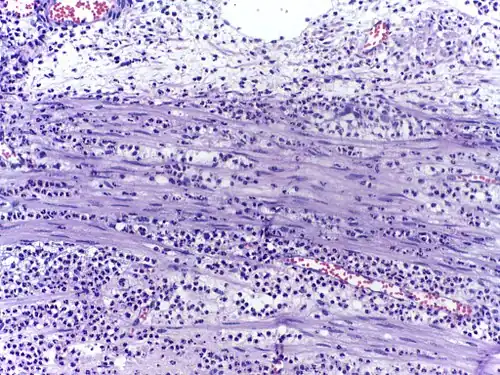

Воспалённые или повреждённые участки соединительной ткани требуют немедленной миграции разнообразных лейкоцитов, в том числе нейтрофилов, в очаг повреждения для удаления патогенных микроорганизмов и восстановления ткани. Наиболее хорошо процесс миграции в ткани изучен для нейтрофилов, которые прибывают в очаг воспаления первыми, существенно быстрее моноцитов, и способны развивать защитные метаболические реакции (в частности, «окислительный взрыв», сопровождающийся продукцией активных форм кислорода) в течение секунд. Активация нейтрофилов сопровождается в первую очередь высвобождением содержимого секреторных гранул. При развитии локального воспаления макрофаги, активированные бактериями или повреждениями ткани, выделяют провоспалительные цитокины, такие как IL-1 или фактор некроза опухоли α (TNF-α). Также к факторам хемотаксиса нейтрофилов относят компоненты комплемента, вещества, выделяемые тучными клетками, иммунные комплексы, эндотоксины и бактериальные пептиды, а также наполненные лизосомы, выходящие в ткань при распаде погибших нейтрофилов и макрофагов[33]. Под действием провоспалительных цитокинов в эндотелиальных клетках, выстилающих ближайшие к очагу воспаления посткапиллярные венулы, увеличивается количество селектинов на поверхности, обращённой в просвет сосуда. Нейтрофилы, циркулирующие в посткапиллярных венулах и имеющие подходящий набор поверхностных гликопротеинов, связываются с селектинами на поверхности эндотелиальных клеток. На данном этапе связывание с эндотелием непрочное, и нейтрофилы продолжают «катиться» по поверхности эндотелия. Провоспалительные цитокины запускают экспрессию интегринов в катящихся нейтрофилах и лигандов интегринов, известных как ICAM-1, на поверхностях эндотелиальных клеток. В то же время межклеточные контакты между клетками эндотелия ослабляются, и эндотелий становится более проницаемым. За счёт интегринов нейтрофилы прочно связываются с эндотелием и прекращают качение, и в конечном счёте приступают к прохождению через эндотелий с помощью псевдоподий (этот процесс известен как диапедез). Проникновение нейтрофилов через эндотелий облегчается благодаря длинному и сегментированному ядру. Прохождение нейтрофилов через эндотелий и дальнейшая миграция к очагу воспаления стимулируются хемокинами[34]. Базальные мембраны нейтрофилы преодолевают благодаря выделению содержимого желатиназных гранул[35].